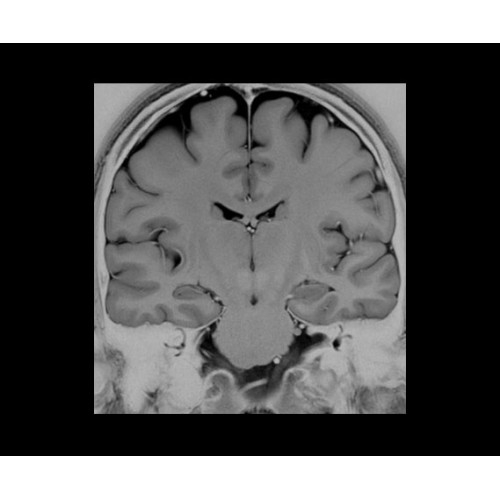

• Специальный пакет приложений для измерения и сравнения объемных изображений ЦНС с нормами поможет вам в диагностике нейродегенеративных заболеваний, а дополнительные инструменты визуализации — в постановке точного диагноза с помощью бета-амилоидов и радиоизотопных маркеров ФДГ.